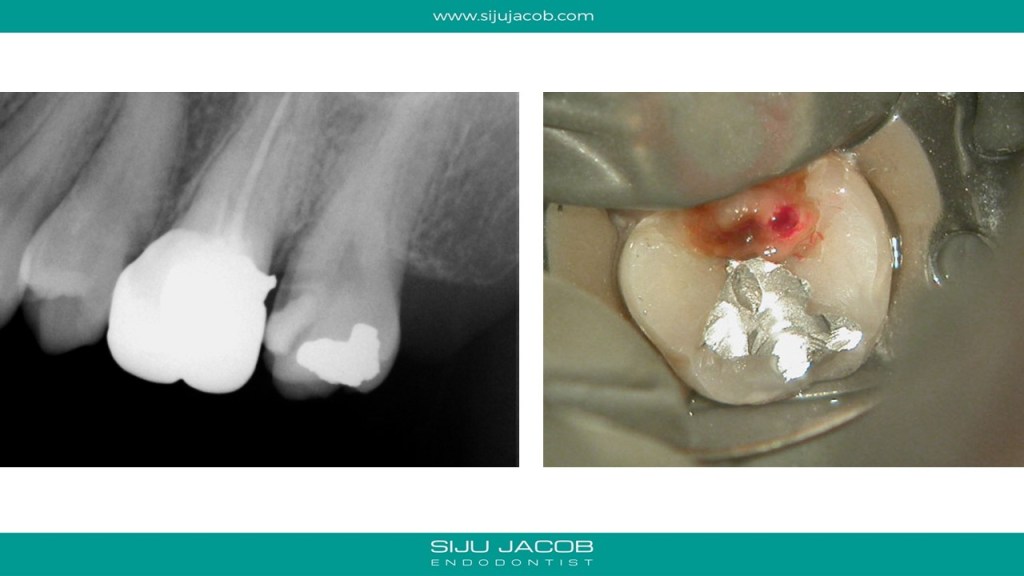

We often see maxillary second molars, which, at first glance seem to have just 2 canals, one Buccal and one palatal. A closer examination of the Buccal canal will often reveal bifurcation into two canals, DB and MB. Here is one such case.